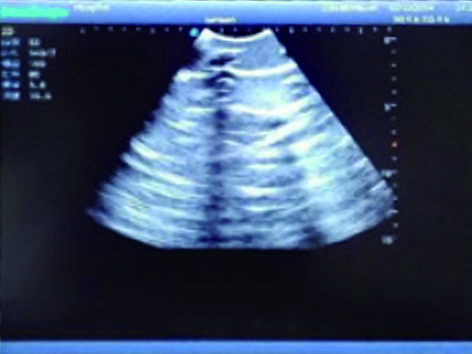

3)  Showing clear and real images of the tissues and organs (including muscle and connective tissue, air-containing lung tissue, pleural structure)

· Ultrasound diagnosis before operation